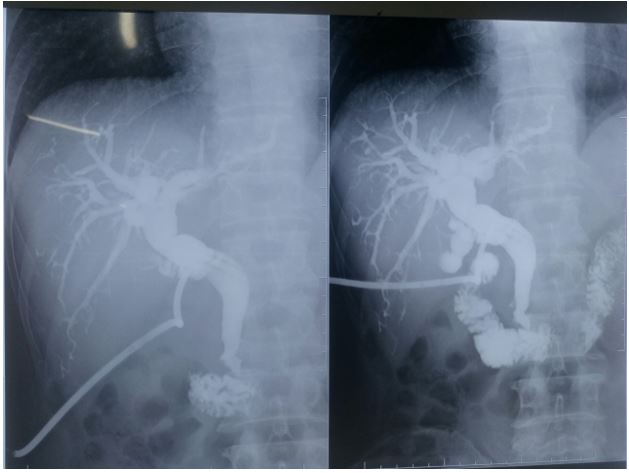

Bệnh nhân trung tiện sau 24h, dẫn lưu Kehr lưu thông tốt. Sau mổ 4 ngày chụp đường mật qua Kehr không rò mật, đường mật trong gan không viêm, sạch sỏi.

Hình ảnh chụp đường mật qua Kehr